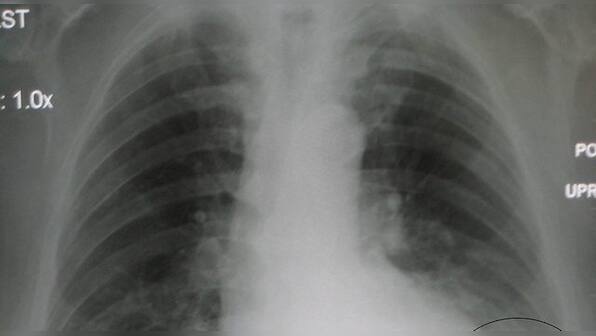

An IIT-Roorkee professor claims to have developed a software which can detect COVID-19 within five seconds using an X-ray scan of the suspected patient. The professor, who took over 40 days to develop the software, has filed a patent for the same and has approached the Indian Council of Medical Research (ICMR) for a review. Kamal Jain, a professor at the institute’s civil engineering department, claims that the software will not only reduce testing costs but will also reduce the risk of exposure to healthcare professionals. So far, there is no verification of his claim by a medical institution. [caption id=“attachment_8296261” align=“alignnone” width=“1280”]The pneumonia caused by COVID-19 is very severe and it affects the lungs completely. Image credit: Wikipedia The pneumonia caused by COVID-19 is very severe and it affects the lungs completely. Image credit: Wikipedia[/caption] “I first developed an artificial intelligence-based database after analysing over 60,000 X-ray scans, including those of COVID-19, pneumonia and tuberculosis patients to differentiate between the kind of chest congestion suffered in the three diseases. I also analysed the chest x-ray database of the United States’ NIH Clinical Center,” Jain told PTI. “Using the software developed by me, the doctors can simply upload pictures of an individual’s X-ray. The software will not only classify whether the patient has any sign of pneumonia, it will be able to tell whether it is due to COVID-19 or other bacteria and also measure the severity of the infection. The results can be processed within five seconds” he added. Jain said the software can help in accurate preliminary screening which can be supplemented by clinical testing for those tested positive for the deadly virus. “The pneumonia caused by COVID-19 is severe than other bacteria as it affects the lungs completely than smaller portions of lungs in other cases. The software will analyse bilateral opacity, pattern of fluid build-up in lungs and nature of clump or clot if any,” the professor said. “Similar kinds of experiments are being conducted by the University of Amazon in the United States but there has not been a breakthrough yet,” he claimed. According to the Union Health Ministry, the death toll due to COVID-19 rose to 718 and the number of cases to 23,077 in the country on Friday. The number of active COVID-19 cases is 17,610 as 4,748 people have been cured and discharged, and one patient migrated, it said. The ICMR said a total 23,502 samples have been confirmed positive for coronavirus so far.